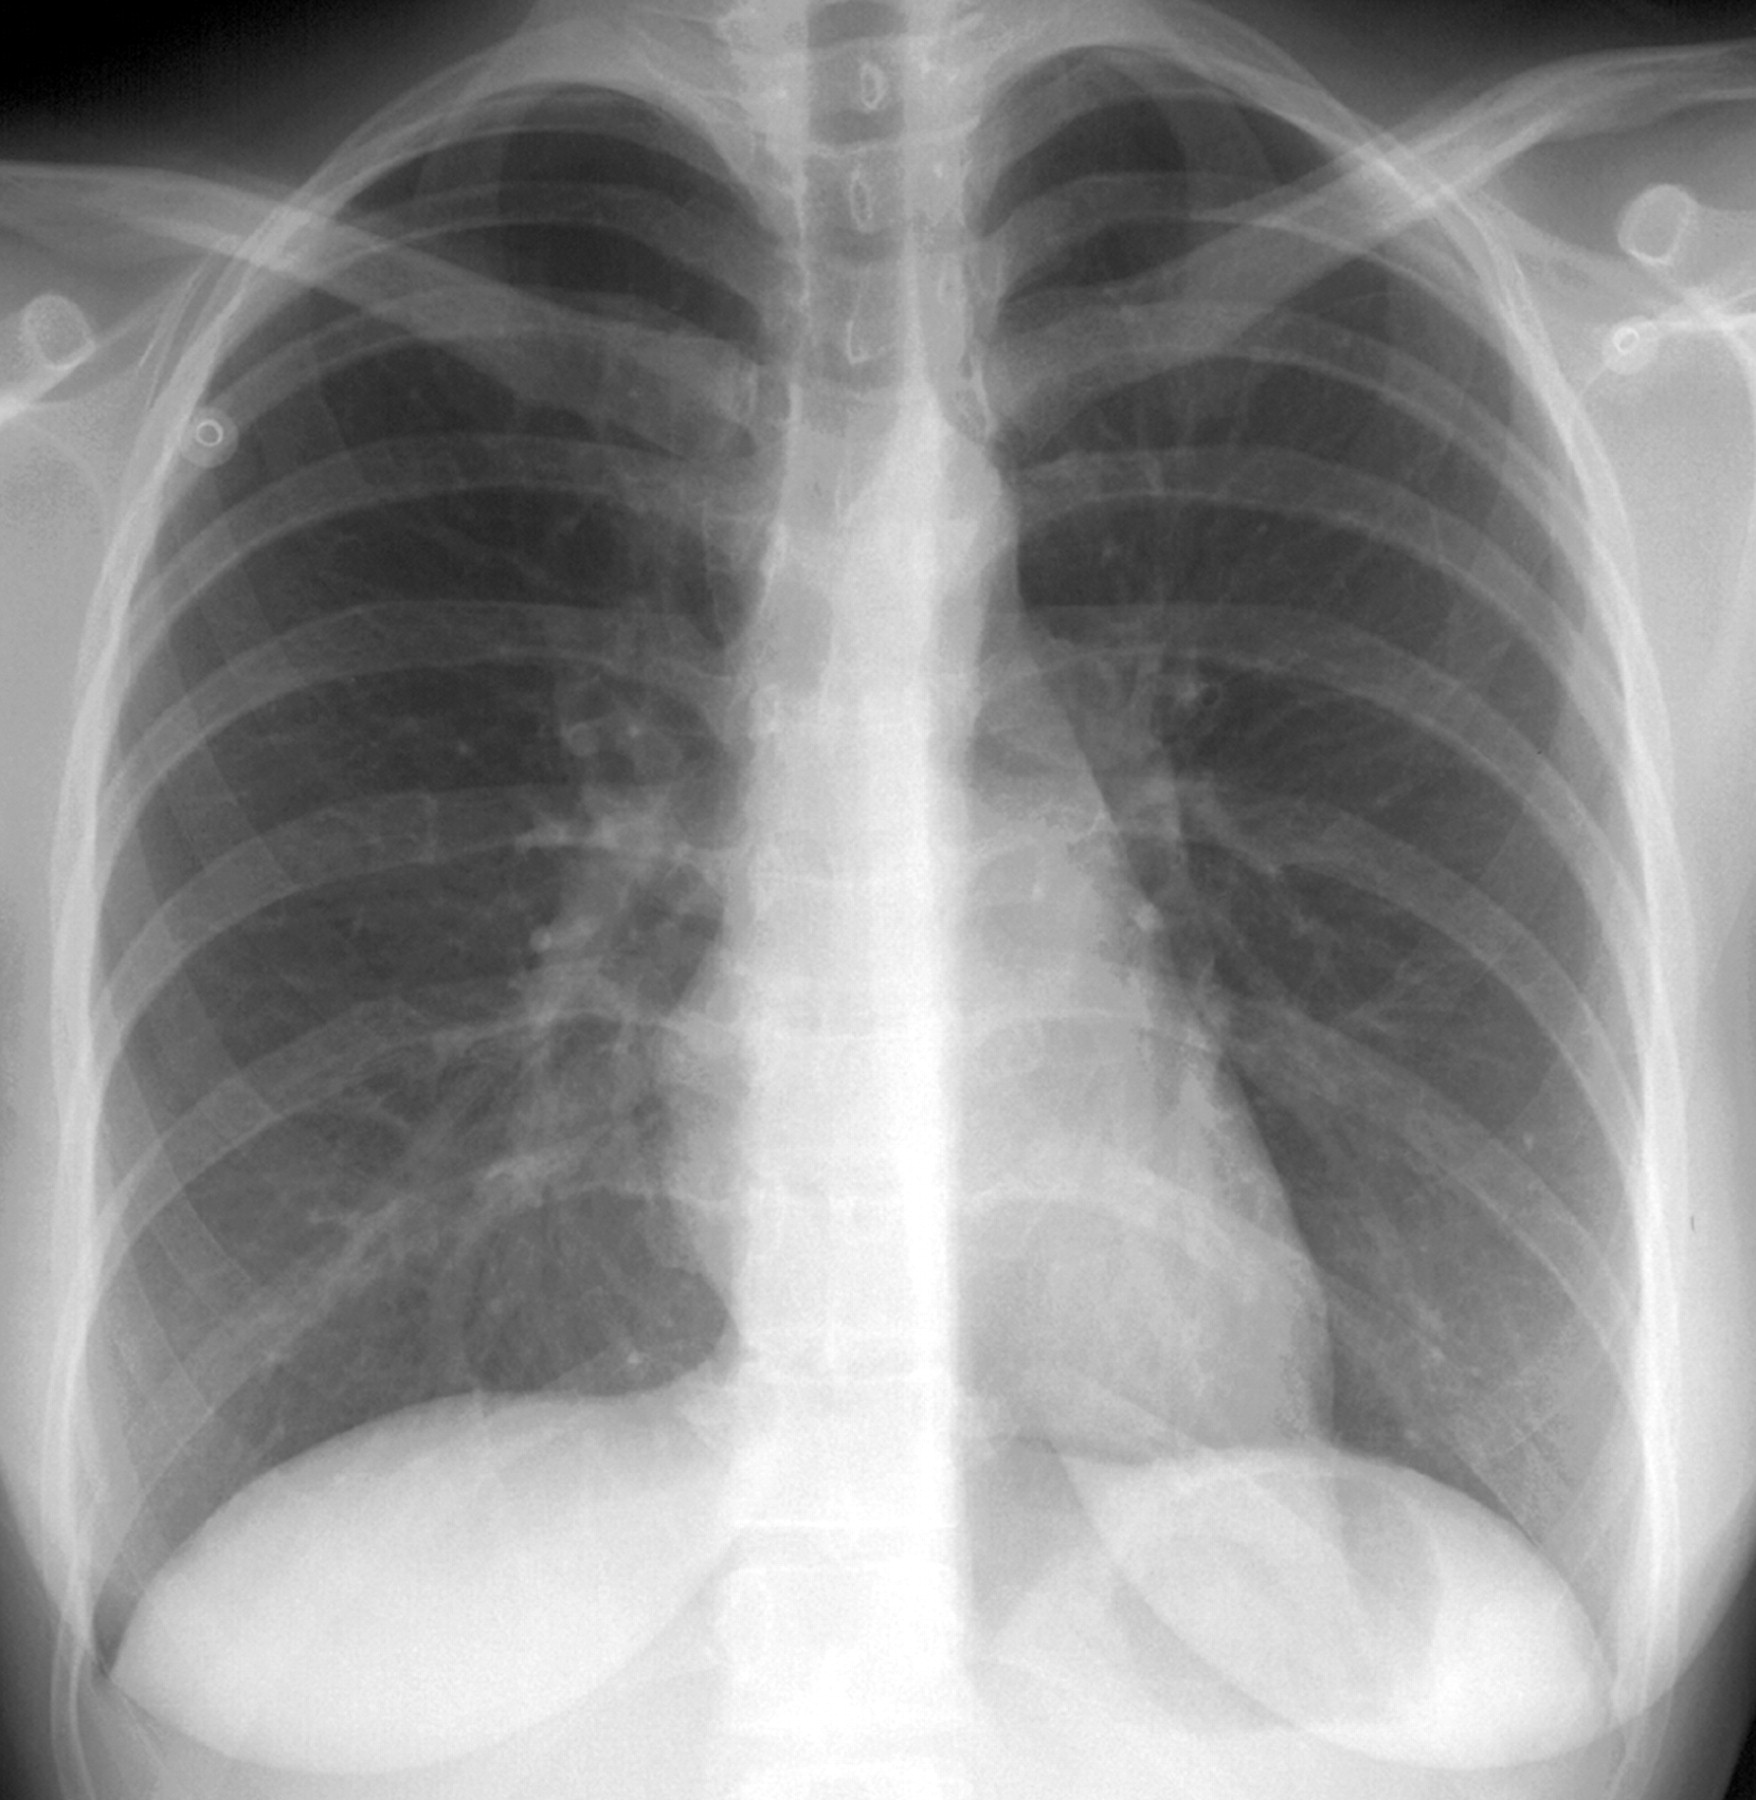

При поступлении одышка, кашель, Т до 37. "Рентгенкартина пневмонии справа, пневмосклероз, эмфизема. Киста, булла слева?" Прошу прощение за качество, снимки"с рук".

По "просьбам трудящихся" не выкладываю все сразу. Но уж ОЧЕНЬ эмфизема, режимы выдал - экспонометр("на среднего"), проявка - автомат. Снимки в реале - темнее ночи. Что тут больше всего смущает справа?

Ссылки на КТ еще не смотрел, но давайте разберемся по классике (хотя из-за качества не хочется :(

На фоне эмфиземы и булл имеется размытая интенсивная инфильтрация в S8 справа и гидроторакс в наддиафрагмальной зоне. НО... Уровень-то горионтальный, значит есть сообщение с воздухом. Пути два: снаружи (пункция) и изнутри (прорыв буллы, абсцесса, кисты). На реформатах жидкости нет.

И еще вопрос: где на РГ центральный-то? рак. Только небольшое расширение и кальцинаты левого корня.

Добавила аксиалы с видео в начале темы. По КТ: ну, буллы, ну, компрессия нижней доли и неполная - средней. Гидропневмоторакс справа. Эмфизема. Рака не увидела.

Ну, рака бы я конечно не поставил. КТ-признаки эмфиземы легких, буллезной эмфиземы, пневмогидроторакса в переднем отделе справа; сзади справа, считаю большая киста/кисты с уровнем жидкости.